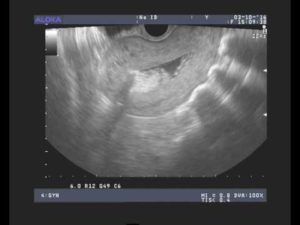

С такими признаками нужно срочно обращаться в клинику. Гинеколог назначит после осмотра ультразвуковое исследование, в ходе которого будет видно внутри осталась плацента или нет. Чтобы устранить последствия, проводится чистка под общим обезболиванием.

5 – 7 дней по окончании родовой деятельности выпадают сгустки крови. Затем они принимают мажущий характер и совсем исчезают. Если спустя 2 – 3 недели изменений не наблюдается, кровь продолжает вытекать, возможно, образовался полип. Когда плацента полностью не вышла после родов, УЗИ показывает увеличенную в размерах матку. Поэтому обильные выделения должны насторожить.

- Ультразвуковое исследование.

Если у вас продолжается обильное кровотечение в течение нескольких дней или недель после родов, вас направят на УЗИ чтобы выявить, не остались ли фрагменты плаценты в матке. Если подозрения подтвердятся, вас направят в больницу для хирургического удаления остатков плаценты из полости матки. Она проводится под анестезией и сопровождается введением антибиотиков.

Чистка матки проводится после родов, если в ней остались части плаценты или скопились сгустки крови. Обнаружить остатки можно на плановом ультразвуковом исследовании, которое проводят после родов.

Отличительной чертой данного заболевания является трудность в его диагностике, потому что начальная стадия приходится на послеродовые кровотечения, характерные для этого периода. Главной причиной полипов считается аборт или выскабливание в анамнезе. Обнаружить плацентарный полип можно только с помощью ультразвукового исследования.